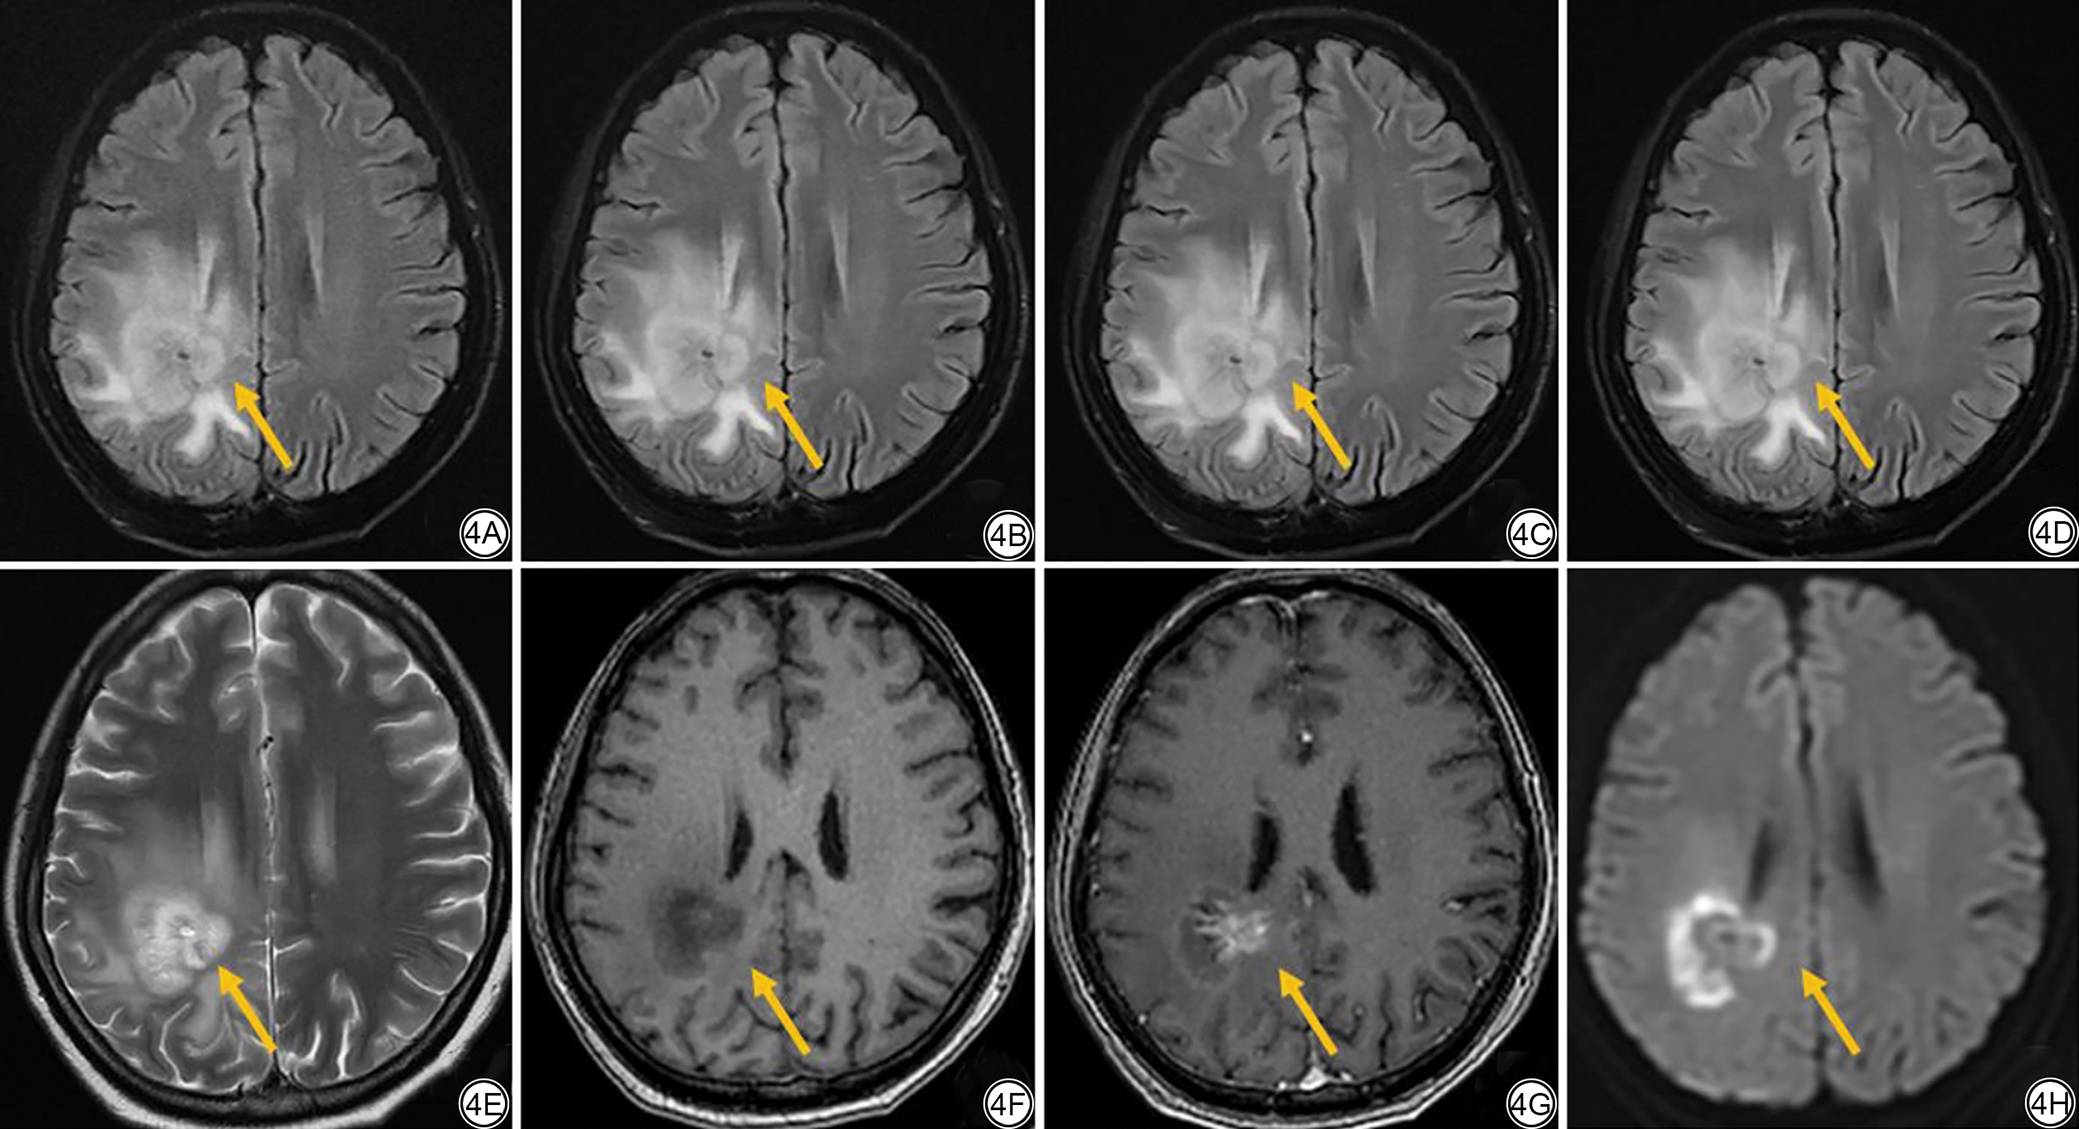

各组图像定性评价结果详见表4图3。PI-DL4组在图像锐利度、噪声和整体图像质量均优于NDL、PI-DL2和PI-DL3组(两两比较P<0.05)(图4)。PI-DL4与PI-DL3组在灰白质对比度、病变显示以及诊断信心差异无统计学意义(P>0.05);PI-DL2与NDL组在所有定性指标差异均无统计学意义(P>0.05);四组图像在伪影方面的评分差异无统计学意义(P>0.05)。另外,少数患者DL等级4病变边缘对比度下降(图5)。

图4  女,49岁,病理诊断为脑胶质瘤,T2-FLAIR图像上可见一高信号占位性病变,弥散受限,增强序列可见明显强化。4A:NDL组常规T2-FLAIR图像,噪声较大,病变(黄箭)显示较好,评分为整体图像质量3分,病变显示3分,诊断信心3分;4B:PI-DL2组快速T2-FLAIR DL重建等级2图像,噪声较小,病变显示较好,评分为整体图像质量4分,病变显示4分,诊断信心4分;4C:PI-DL3组快速T2-FLAIR DL重建等级3图像,无明显噪声,病变显示好,评分为整体图像质量5分,病变显示5分,诊断信心5分;4D:PI-DL4组快速T2-FLAIR DL重建等级4图像,无明显噪声,病变显示好,评分为整体图像质量5分,病变显示5分,诊断信心5分;4E:T2加权图像;4F:T1加权图像;4G:增强T1加权图像;4H:弥散加权图像。T2-FLAIR: 液体衰减反转恢复;PI:并行采集;DL:深度学习。

Fig. 4  Female, 49 years old, Pathological diagnosis was glioma of the brain, a high signal mass lesion can be seen on the T2-FLAIR image, restricted diffusion with obvious enhancement on contrast-enhanced imaging. 4A: Conventional T2-FLAIR image with traditional reconstruction in the NDL group, with higher noise, the lesion display is good (yellow arrow), with a score of 3 for overall image quality, 3 for lesion display, and 3 for diagnostic confidence. 4B: Fast T2-FLAIR image reconstructed with DL level 2 (PI-DL2 group), with lower noise, and good lesion display. The score is 4 for overall image quality, 4for lesion display, and 4 for diagnostic confidence. 4C: Fast T2-FLAIR image reconstructed with DL level 3 (PI-DL3 group), with no obvious noise. The lesion is well displayed, with a score of 5 for overall image quality, 5for lesion display, and 5 for diagnostic confidence. 4D: Fast T2-FLAIR image reconstructed with DL level 4 (PI-DL4 group), with no obvious noise. The lesion is well displayed, with a score of 5 for overall image quality, 5 for lesion display, and 5 for diagnostic confidence. 4E: T2-weighted image. 4F: T1-weighted image. 4G: T1-weighted contrast-enhanced image; 4H: diffusion-weighted image. T2-FLAIR: T2-fluid attenuated inversion recovery; PI: parallel imaging; DL: deep learning.